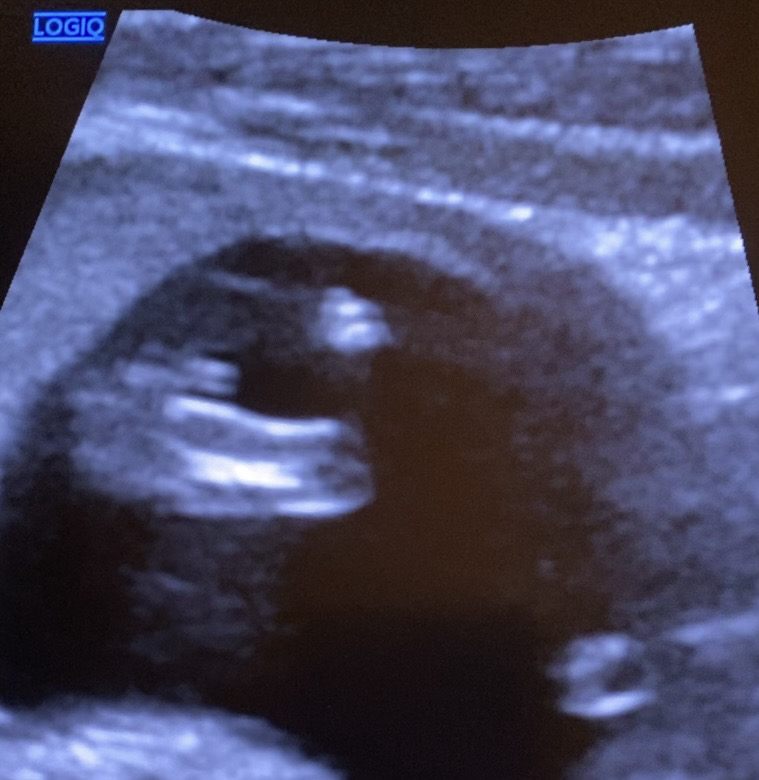

이제 막12주 됫는데 이건멀까요..?

설마 아들인가요? 아님 두갈래는 딸이라는 데 아직은 알수없겟져??

딸같은데.... 저는 아들 둘에 셋째 맘이에요 아들은 12주에 이미 삼각점이 ㅋㅋ 뫼산 모양으로 동글동글하게 있어요 저도 셋째가 애매해서 확정 못받았네요ㅠ 두 형아는 12주에 아들맘 확정받았는데 ㅜㅜ 희망고문...ㅋㅋㅋㅋㅋㅋㅋ